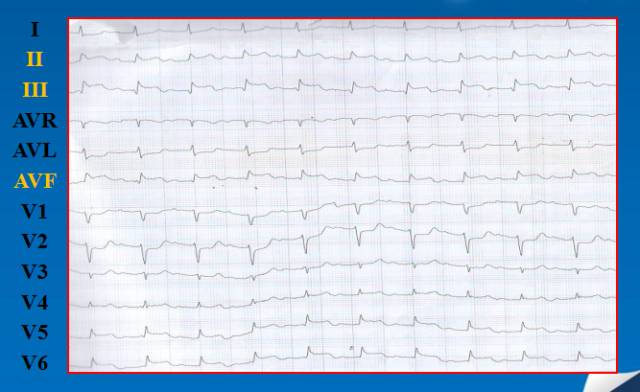

患者于4小时前自感胸前区疼痛,伴胸闷及左肩部放射痛, 不伴恶心、呕吐等,至我院急诊科行心电图示“II,III,aVF导联ST段抬高”,遂以“急性冠脉综合征(ACS) 急性下壁ST段抬高型心肌梗死”收入

急诊心电图